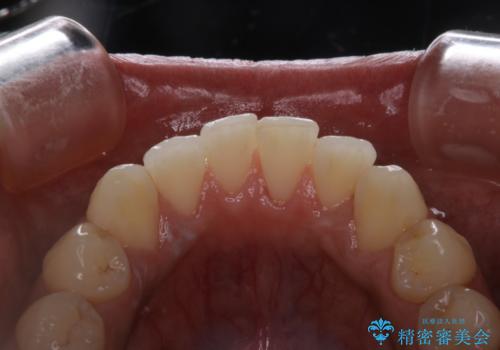

タバコによるヤニ、着色、歯の汚れをPMTC(60分コース)で除去。

タバコのヤニを取って歯を白くしたい